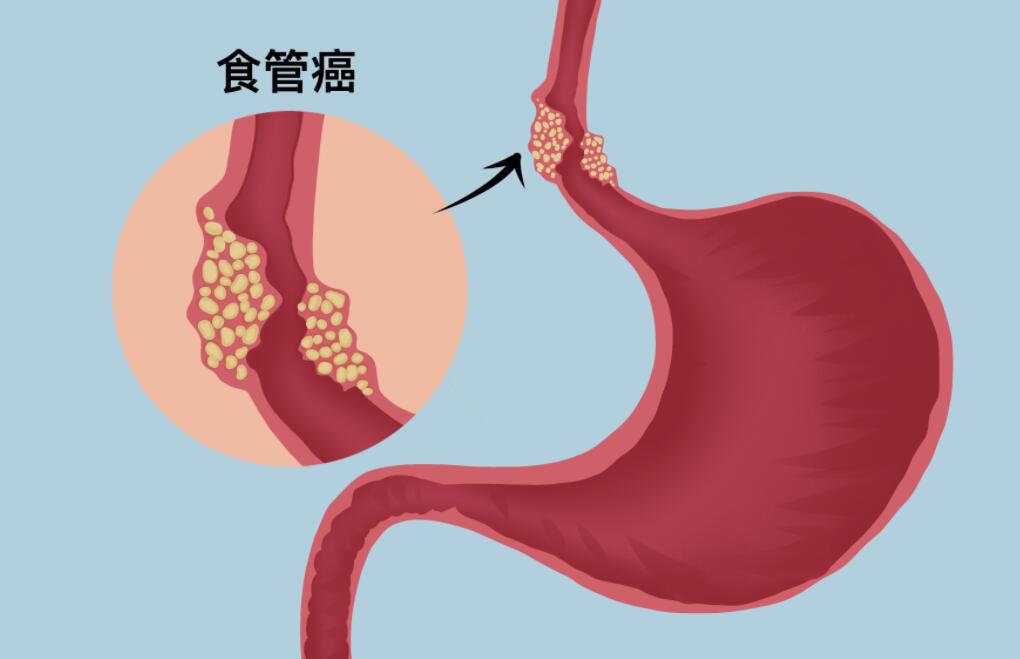

食道癌是非常折磨人的癌症,首先食道癌是食道出现癌细胞,食道癌可以说是最痛苦的癌症了,从发病开始会出现吞咽困难。

随着病情的加重,病程的延长,开始只是吞咽食物有困难后续会变成饮水都困难甚至吞咽都不能进行,只能靠输液延续生命,食道癌患者的死因多是因为饥饿导致的。